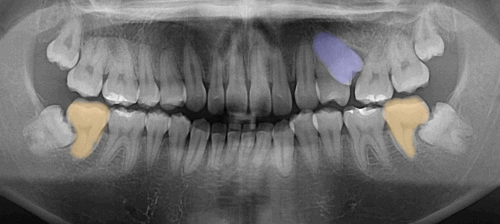

| 1. 검진

초진 검사에서는

정밀한 진단이 가장 중요해요.

22.03.26

먼저 구내 촬영과 파노라마 촬영을 통해

매복된 치아의 정확한 위치와 방향을 파악합니다.

또한 3D CT 촬영으로 뼈의 상태와

주변 조직과의 관계도 정확히 분석하죠.

절단연 교합의 경우,

단순히 치아 배열만의 문제인지

아니면 골격적인 문제를 동반하는지

감별해야 됩니다.

골격적인 문제를 동반하면

치료 방법이 달라질 수 있거든요.

정중선 불일치는

윗니와 아랫니 각각의 문제인지,

아니면 전체적인 안면 대칭과 관련된 문제인지

종합적으로 판단합니다.

심각한 치근 흡수 문제는

흡수 정도를 정확히 측정하여

해당 치아를 살릴 수 있는지 여부를

결정해야 됩니다.